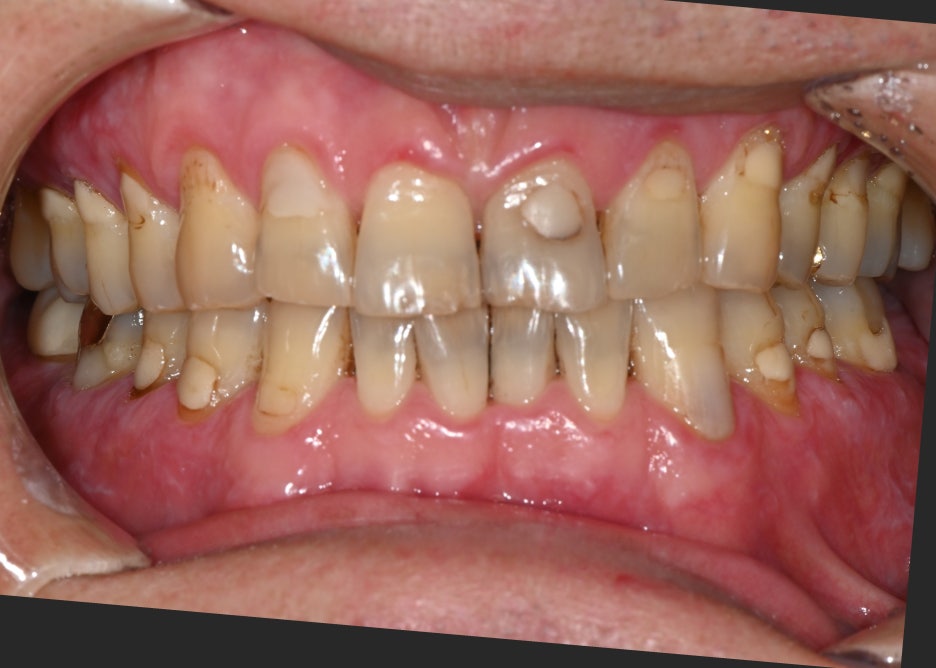

The patient visited with the chief complaint that “the lower left molar was extracted a long time ago, and lately I’ve been chewing only on the other side, so my jaw feels uncomfortable.”

Because the tooth had been missing for a long time, the bite was unbalanced on both sides, and the patient said food often got stuck and the gums felt uncomfortable.